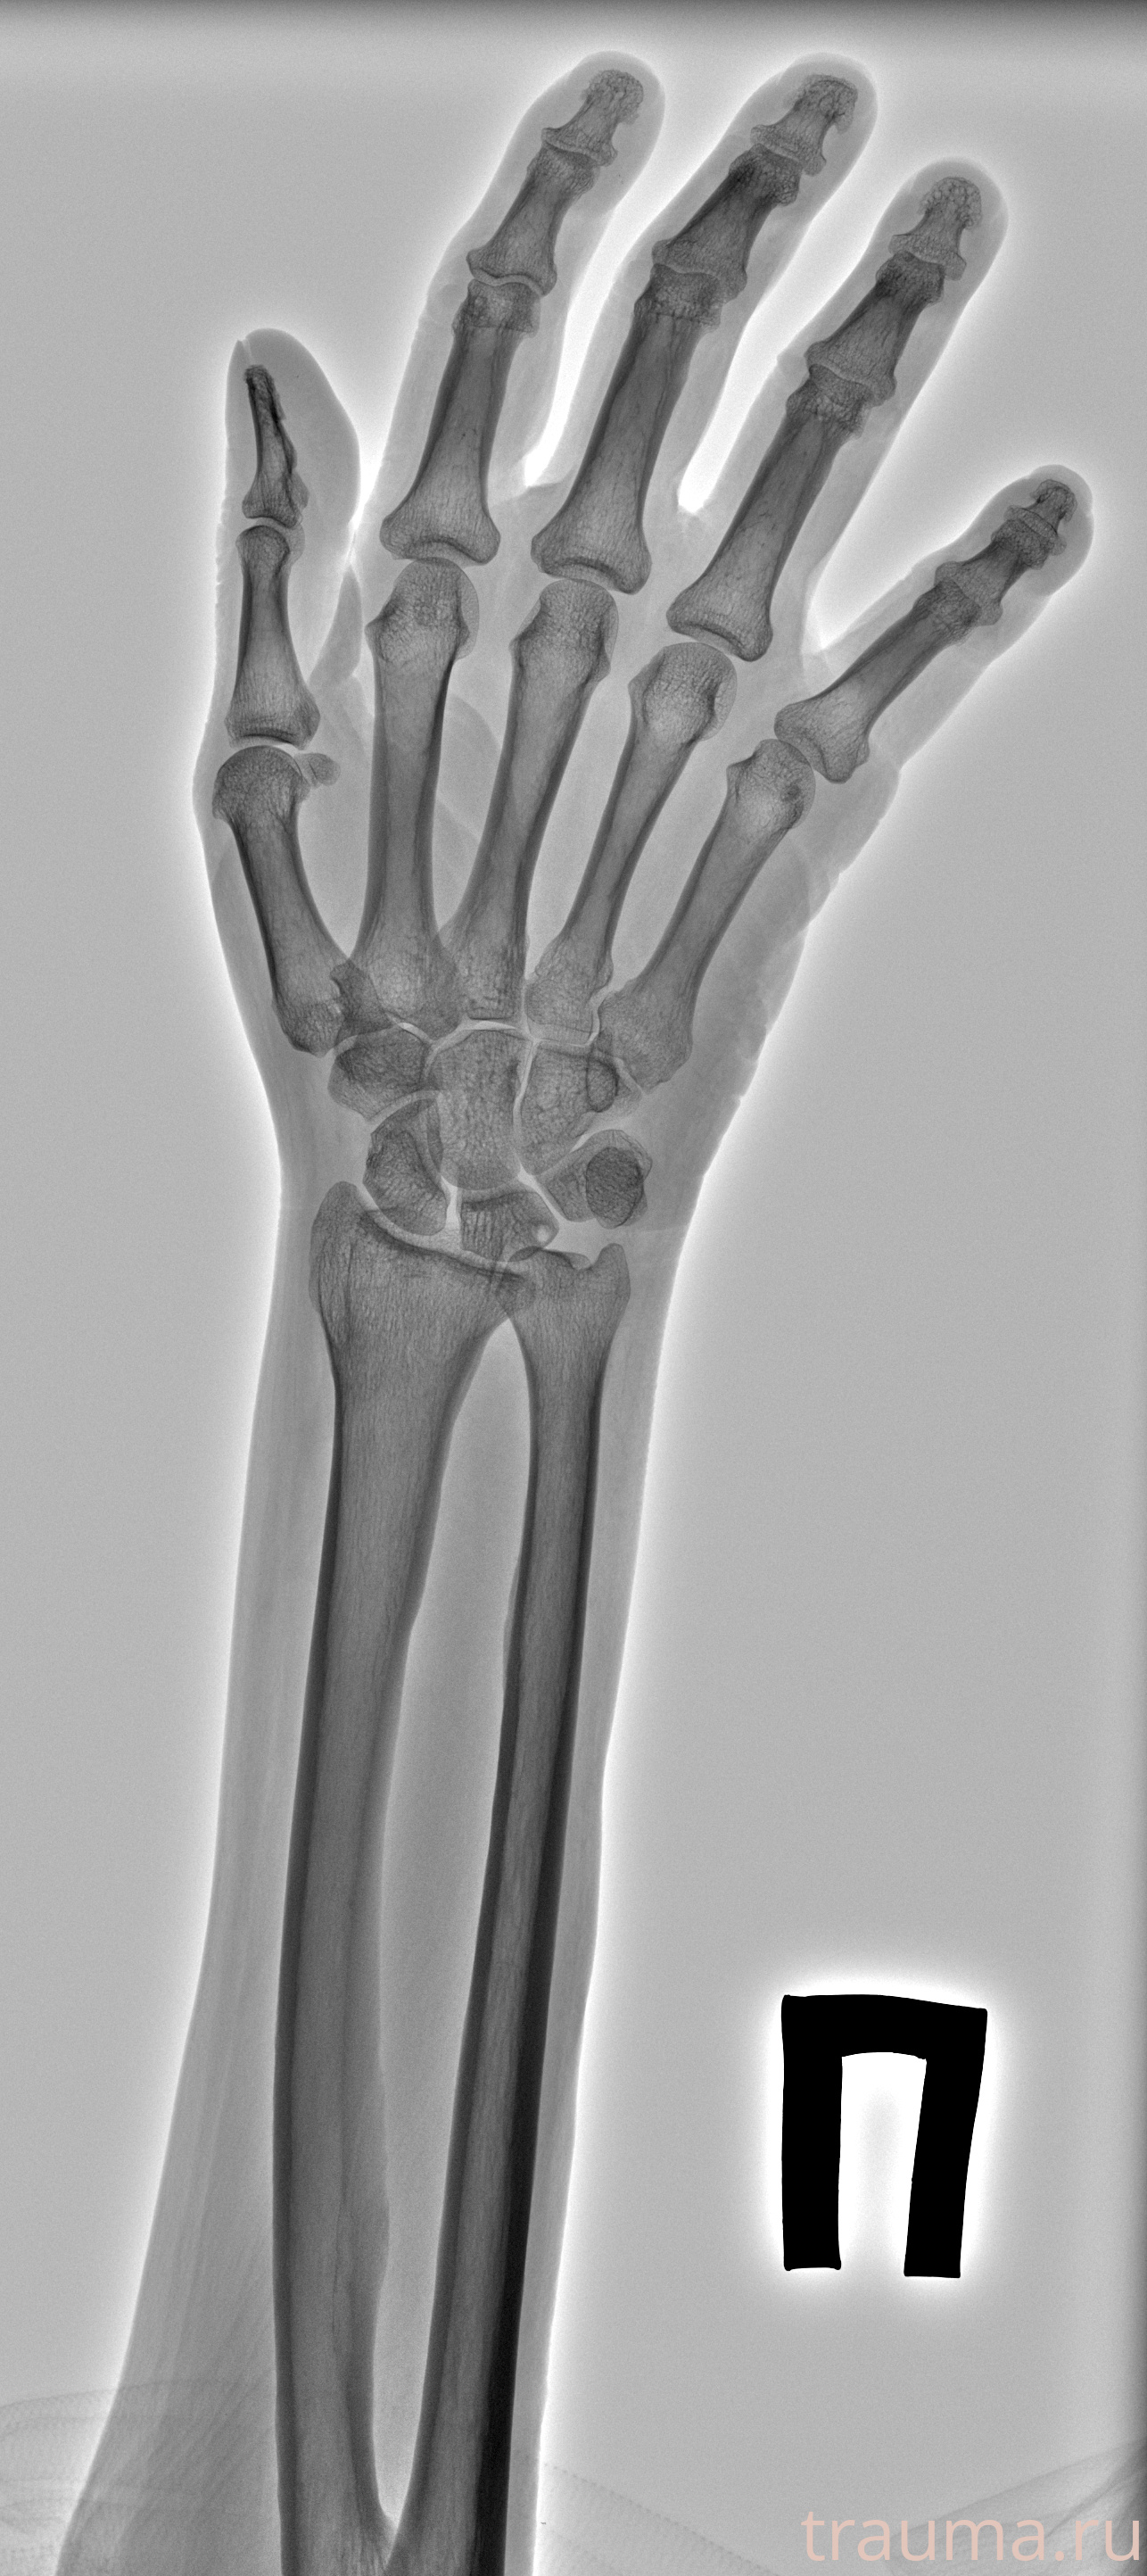

Рентгенограммы

Рентген на дому: по вашему адресу приезжает врач-рентгенолог, травматолог-ортопед с мобильным рентгеновским аппаратом, проводит диагностику травмы или заболевания, делает необходимые рентгенограммы, дает рекомендации по дальнейшему лечению. Получить качественные снимки в домашних условиях возможно благодаря уникальной методике, разработанной МосРентген Центром для института  Склифосовского